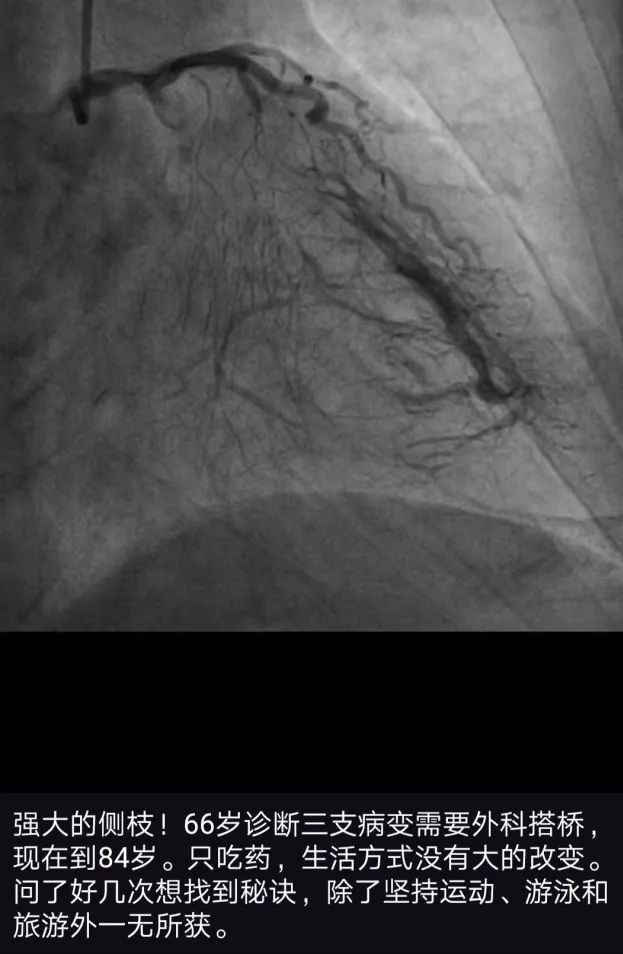

这是我朋友圈发的一个病例,患者从年轻时就坚持锻炼,尤其是游泳。三支慢性完全闭塞病变发现近 20 年,生活质量竟然没什么大影响。侧枝循环在 CTO 司空见惯,…